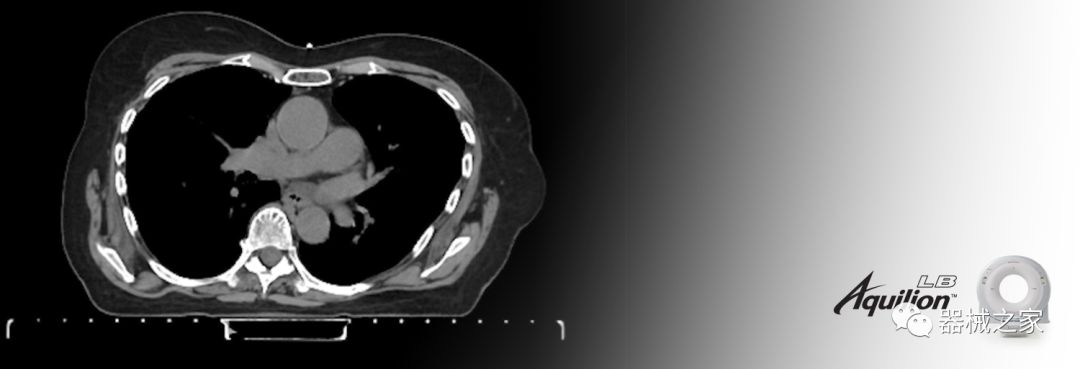

佳能醫(yī)療的Aquilion Lightning 80掃描儀還以緊湊,經(jīng)濟(jì)的包裝提供高質(zhì)量的成像。Aquilion Lightning 80旨在可靠,高效地運(yùn)行,在繁忙的環(huán)境中生成高質(zhì)量的圖像。

兩個(gè)CT系統(tǒng)均采用0.5 mm x 80排PUREViSION探測(cè)器技術(shù)(可配置并從80-160現(xiàn)場(chǎng)升級(jí)),78 cm孔徑,50 cm視野,AIDR(自適應(yīng)迭代劑量減少)3-D和SEMAR(單個(gè))能量金屬神器減少)技術(shù)。

Aquilion LB專為滿足腫瘤學(xué)挑戰(zhàn)而設(shè)計(jì),同時(shí)優(yōu)先考慮患者護(hù)理。Aquilion LB的內(nèi)徑為90 cm,能夠幫助復(fù)雜的患者設(shè)置并提高患者的舒適度。CT模擬定位可以輕松鏡像放射治療定位,更加自信。該系統(tǒng)采用0.5 mm x 16排(32層)PUREViSION探測(cè)器技術(shù),70 cm視野,AIDR 3D和SEMAR技術(shù)。